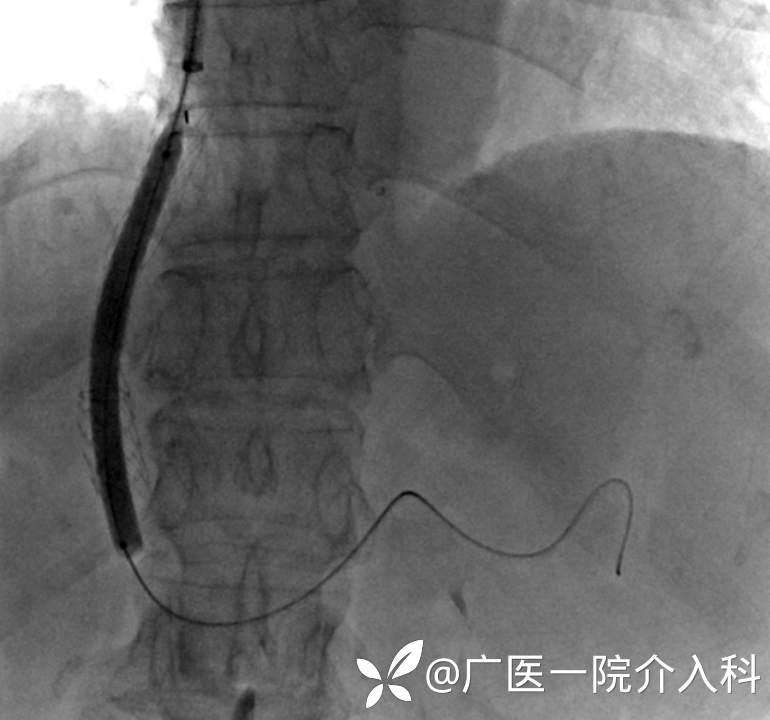

治疗方案:经熊斌教授指导,肝肠外科郭健副主任医师为患者进行经颈动脉内肝门体静脉分流术(TIPS)。

经颈静脉肝内门体支架分流术(TIPS)